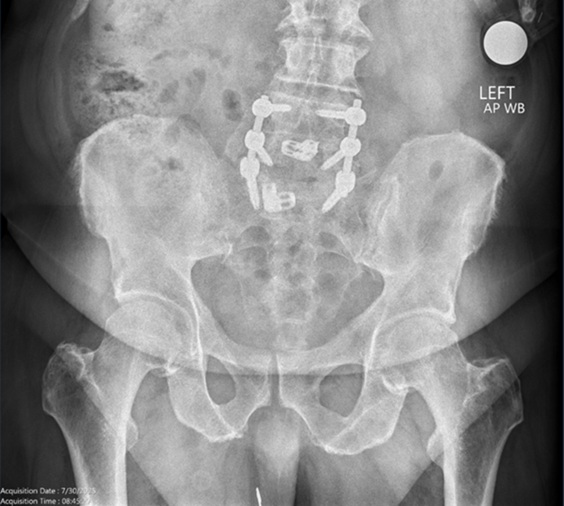

His radiographs in the clinic revealed left hip degenerative joint disease. Additionally, his pre-operative hip MRI revealed significant narrowing of the joint space and femoral head edema securing the diagnosis of degenerative joint disease. His exam was significant for limited internal rotation to no more than 5 degrees, a positive stinchfield test and an antalgic gait.

Radiographs are noted below. Pre-op, Post-op and intra-op radiographs are found below as well as the pre-op MRI.

Figures 1, 2 and 3. AP of the Pelvis, AP of the Left Hip, and a Frog Leg Lateral of the Left Hip demonstrating left hip osteoarthritis.

Pre-op Radiographs:

Figure 1.